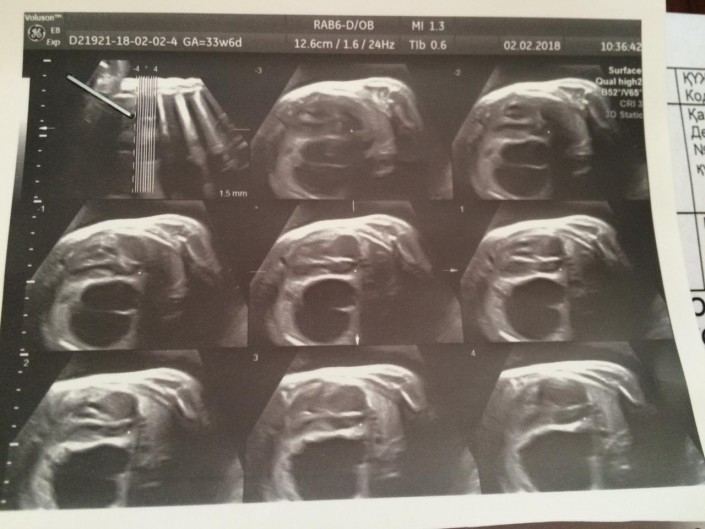

Снимок УЗИ. Киста в левом легком Яна

О диагнозе Павел и Василина не сказали ни родственникам, ни знакомым. Оставшийся период до родов был тревожным и полным неопределенности. Контрольные УЗИ показывали, что киста не рассасывается. Более того, она становилась больше. Все шло к тому, что скорее всего, ребенка придется оперировать. Тем временем, будущие бабушки и дедушки Яна, ничего не подозревая, покупали для крохи первую одежду.